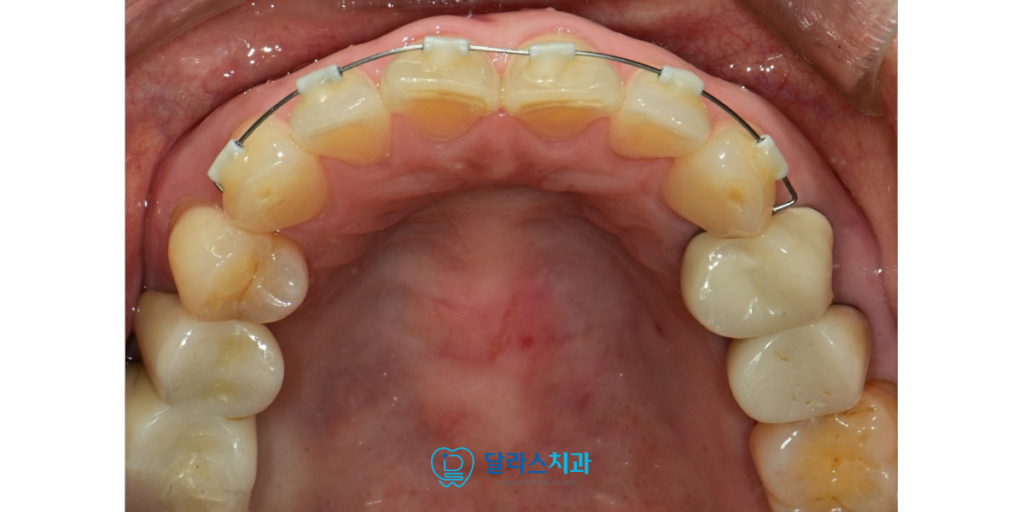

위쪽 치아인 상악의 문제도 함께 해결하기를 원하셨습니다.

상악 역시 치아들이 서로 겹쳐 있는 부분이 있었고

특히 치아들의 높이 차이가 불규칙하여 웃을 때나

대화할 때 심미적으로 아쉬운 부분이 있었기 때문입니다.

이에 따라 상악에도 작은 튜브 모양의 교정 장치를

추가로 부착하여 본격적인 상하악 부분 교정을 진행하였습니다.

상악의 불규칙한 치아 높이를 일정하게 맞추고

겹쳐진 치아들을 제자리로 이동시키는 과정이 이어졌습니다.

이 장치는 크기가 매우 작아 점막 자극이 적고 위생 관리가 쉬워

노원치과 환자분께서 치료 기간 내내 큰 불편함 없이 생활하실 수 있었습니다.

하악에서 시작된 긍정적인 변화가 상악까지 이어지면서

전체적인 미소선이 개선됨과 동시에 양치질이 훨씬

수월해지는 이득까지 얻을 수 있었습니다.

총 치료 기간은 약 5개월이라는 비교적 짧은 시간 내에 마무리되었습니다.